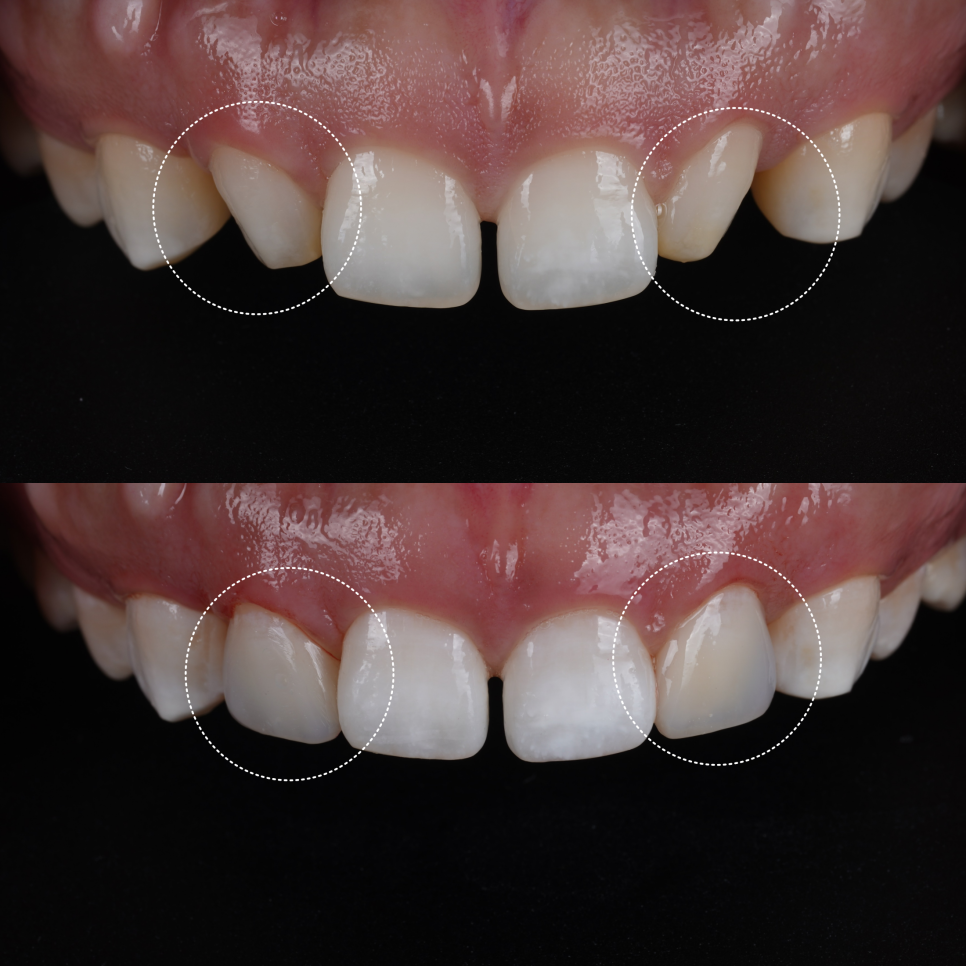

사실 고민의 시작은 ‘벌어짐’이 아니었어요.

가장 먼저 눈에 띈 건, 가운데 앞니 사이가 살짝 벌어져 있었지만 정작 환자분이 처음 꺼낸 말은 이거였어요.

“이 치아가 너무 작아 보여요.”

바로 왜소치였어요. 환자분은 벌어진 것보다 왜소치가 더 거슬린다고 하셨습니다.

그래서 왜소치 먼저 레진 치료를 했습니다.

먼저 크기가 작은 곳부터 정상 비율로 만들 예정이에요.

문제는 왜소치의 각도가 안쪽으로 기울어져있었다는 점입니다.

그리고 왜소치 뒤편으로 공간이 있어서 이 공간까지 메우게 되면 두 번째 앞니가 매우 커질 가능성이 있었죠.

그래서 너무 커지면 뒤쪽을 좀 삭제해서 남겨두는 방향도 설명을 드렸습니다.

환자분은 송곳니와의 사이가 벌어져 있어도 상관없다고 말씀해 주셨습니다.

먼저 요청하신 왜소치 부터 정상 비율로 만들어보고 그 비율을 기준으로 앞니 사이 공간을 어떻게 할지 결정하기로 했어요.

비율과 형태 모두 자연스러움을 목표로 했어요.

삭제는 하지 않고 반대편 측절치와 비율과 곡선만 맞추는 방식으로 진행했습니다.

이때 일부러 “사이를 완전히 꽉 채우지 않는 디자인”을 선택했는데요.

공간을 완전히 닫기보다는 소량의 여유를 남기고, 잇몸선과 치아 윤곽이 자연스럽게 이어지도록 디자인해야 잇몸 건강을 유지하기에 유리하고 위생 관리 또한 수월합니다.

앞니 왜소치 레진 전, 후 / 촬영일 : 251203 / 251203

환자분이 거울을 보시고 “생각보다 티가 안 나네요?”라고 하셨을 때 이 방향이 맞다는 확신이 들었어요ㅎㅎ